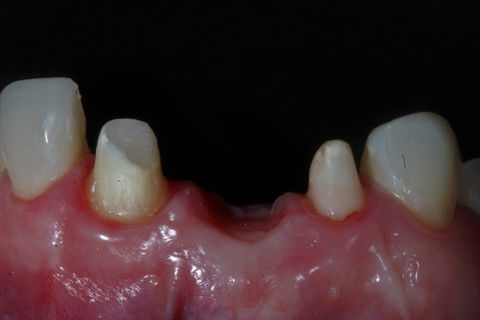

Cirurgia de conjuntivo da região do elemento 11.

Preparos dos elementos do 21 e do 12.